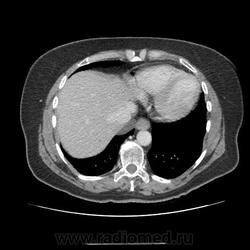

Брюшная полость+контраст. объемное образование в задне-нижнем отделе средостения ( осумкованный плеврит?)

Женщина  64 года. Из анамнеза: находилась на лечении в онкологическом диспансере  с 29.11.13 по 05.12.13. DS: ЗНО маточной трубы I ст T1NxM0 после комбинированного лечения в 2011г. Прогрессирование в 2012г после ПХТ. Ремиссия 1 год. Прогрессирование в 2013г. (увеличение СА 125, мтс в сальник) в процессе ПХТ. Стабилизация. Осложнения: анемия, лекопения, ХПН. MDS аденокарцинома G1. На КТ данных за мтс не обнаружил. В задне-нижнем отделе средостения над левой долей печени образование плотностью +10HU. для липомы высокая плотность, контраст не накапливает, осумкованный плеврит? И в области верхней полой вены циркулярно какой то V что ли?